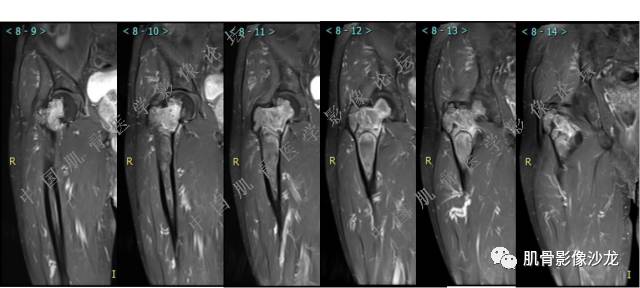

主诉:右侧股骨近端持续疼痛1月余

现病史:1个月前因天气转冷突然右侧股骨疼痛,无乏力麻木,遂就诊于当地医院X线检查发现右股骨异常密度,为进一步诊治来我院。

既往史:高血压史。余无特殊。